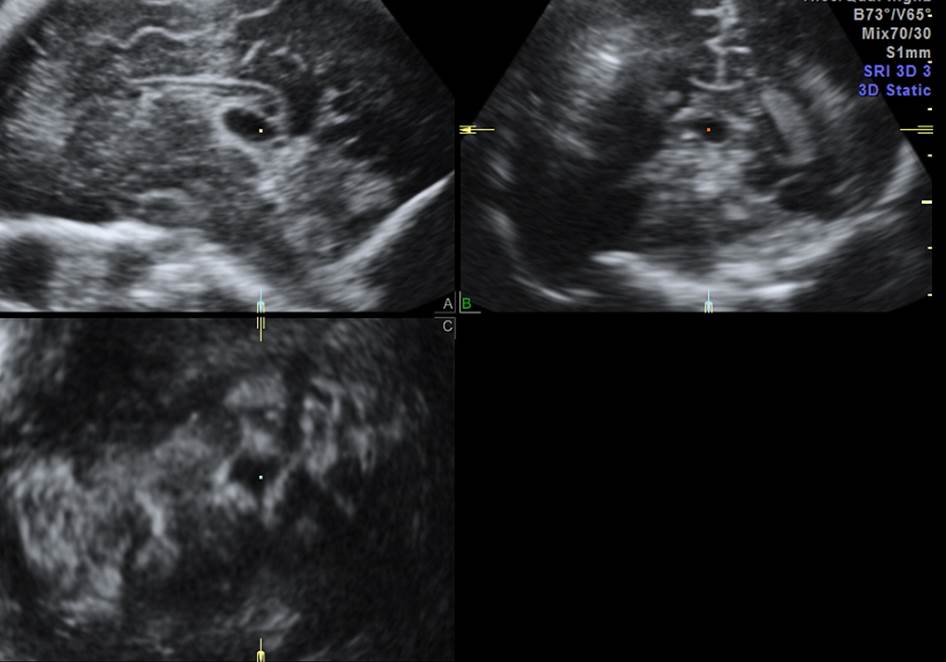

- 30 недель. Диагноз?

Ответ на вопрос 7

- Многокамерная арахноидальная киста.

- Мальформация коры головного мозга. Полимикрогирия.